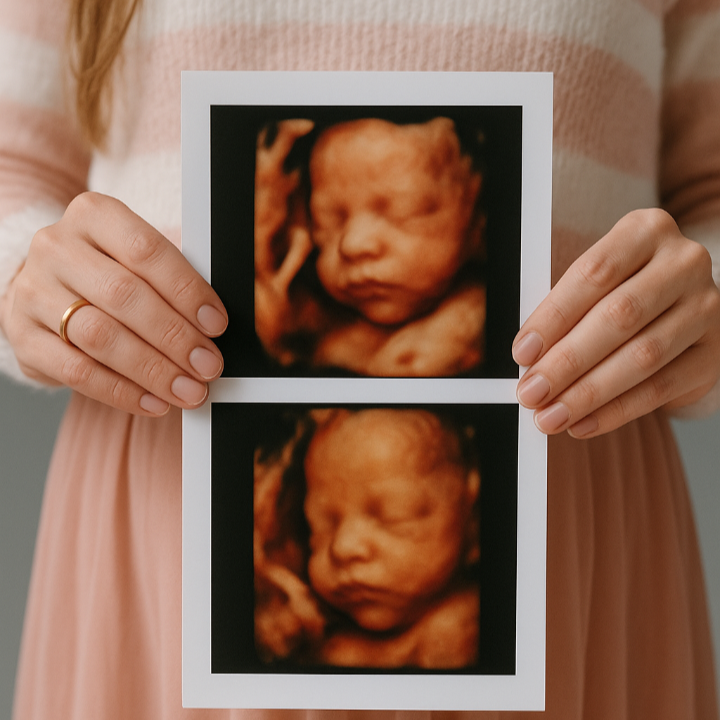

Een pretecho is een echo zonder medische noodzaak. Voor deze echo kun je altijd kiezen, maar hier betaal je ook altijd zelf voor. Je kijkt met deze echo bijvoorbeeld naar de bewegingen, het gezichtje of de handjes en voetjes. Wat je kunt zien hangt af van de grootte en de ligging van de baby. Mocht je de baby in 3D/4D willen bekijken dan is de beste termijn tussen de 26 en 30 weken zwangerschap.

Wij hebben er voor gekozen om geen pretecho’s aan te bieden in onze eigen praktijk. Wij verwijzen je hiervoor naar Eva van Hoorn of een ander echobureau in de buurt.